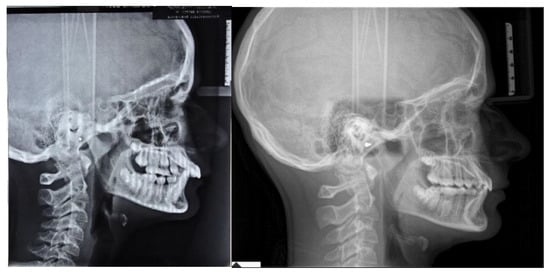

The patient was a 12.7-year-old Caucasian male with a chief complaint of excessive exposure of upper incisors (Figure 1). The general medical history was negative for illness, allergy. The patient did not present any familiarity for Angle Class II malocclusion and had not received any previous orthodontic treatment. Facial photographs revealed a convex profile with a hypodivergent growth pattern. At intraoral evaluation, the patient showed palatal impingement of the mandibular incisors on the palatal mucosa, as well as mandibular lip interposition between upper and mandibular incisors; narrow upper and mandibular arches (maxillary intermolar width-distance between maxillary first molar palatal cusp tips: 43 mm; mandibular intermolar width-distance between the central fossa of mandibular first molars: 46 mm), a bilateral molar and canine Angle Class II relationship, increased overjet and overbite with a deep curve of Spee were observed (Figure 1).

Figure 1.

Pre-treatment intraoral, extraoral photographs and radiographic examination.

In accordance with the Radiographic Guidelines of the British Orthodontic Society (last access: 1 March 2021, https://www.bos.org.uk), lateral cephalometric radiographs were obtained and analyzed. Landmarks and measurements were validated by Shaw et al. [4], and all data were anonymized.

The orthopantomography revealed a late mixed dentition, with the absence of “tooth developmental anomalies” of number, size, shape, eruption, position, structure.

According to Steiner’s cephalometric analysis [5], the patient showed a skeletal Class II relationship (ANB = 6°; Wits = 4 mm). Referring to the anterior cranial base (SN plane: Sella-Nasion), the patient presented a retruded mandible (SNB = 75°) with an increased inclination of upper incisors (U1-SN = 125°; IMPA = 90°) (Figure 1). The overjet and the overbite were also increased at the beginning of treatment (overjet = 8 mm; overbite = 6 mm) (Figure 1).

According to the Sassuoni analysis of vertical facial proportions [6], the patient revealed a skeletal deep bite tendency as the anterior cranial base plane, the Frankfort plane (FH), the palatal plane and the mandibular plane tended to converge far behind the face. However, the mandibular plane and the occlusal plane intersected relatively close to the face, owing to a deep curve of Spee with extrusion of mandibular incisors. (Figure 1). According to Steiner’s cephalometric analysis, it was confirmed that the occlusal plane (OP) was almost parallel to Frankfort’s plane (OP-FH = 2°), and that the maxilla (palatal plane, ANS/PNS) was properly inclined with respect to Frankfort’s plane (ANS/PNS-FH = 4°); moreover, the angle (FMA) between mandibular plane (ML) and Frankfort’s plane (FH) revealed a forward rotation of the mandible at the beginning of the treatment (FMA = 19°).

According to the cervical vertebral maturation method [7], the patient was in a pubertal phase without completing his craniofacial growth (between CS2 and CS3) (Figure 1).